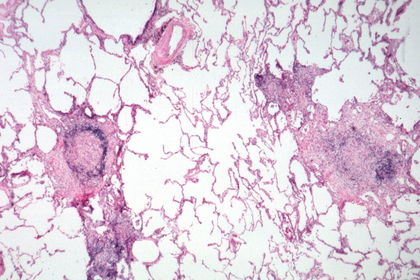

TISSUE TYPE: dots on white page :D... white page= alveolar spaces.. u can see carbon particles (anthracosis)..LUNG PATHOLOGY: inflamatory cells in alveolar spaces .. DIAGNOSIS: acute lobar pneumonia KEY: WHITE BACKGROUND ..

Acute lobar pneumonia